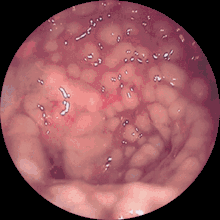

Через токсини, які виділяють клостридії (цитотоксини: токсин А і токсин В), може розвинутися діарея з дуже тяжким перебігом, значною втратою рідини та дегідратацією. Токсини Clostridioides difficile руйнують шари слизової оболонки і спричинюють значне виділення фібрину, відкладання якого в кишечнику при колоноскопії описуються як «котячі голови».

Потовщення кишкової стінки товстої кишки можна побачити при проведенні УЗД та на комп'ютерній томографії. Ендоскопічно спостерігаються світлі відкладення фібрину в товстій кишці, частина з яких плямиста, частина з них злита.